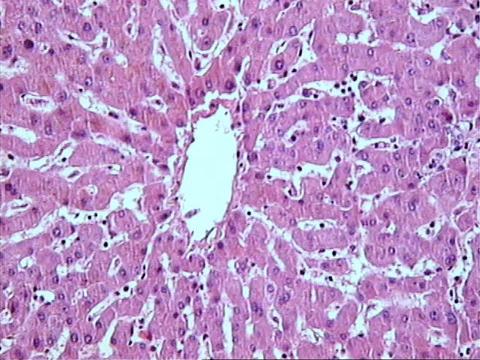

Hígado. Hepatocitos

Las células hepáticas se organizan en cordones radiados.